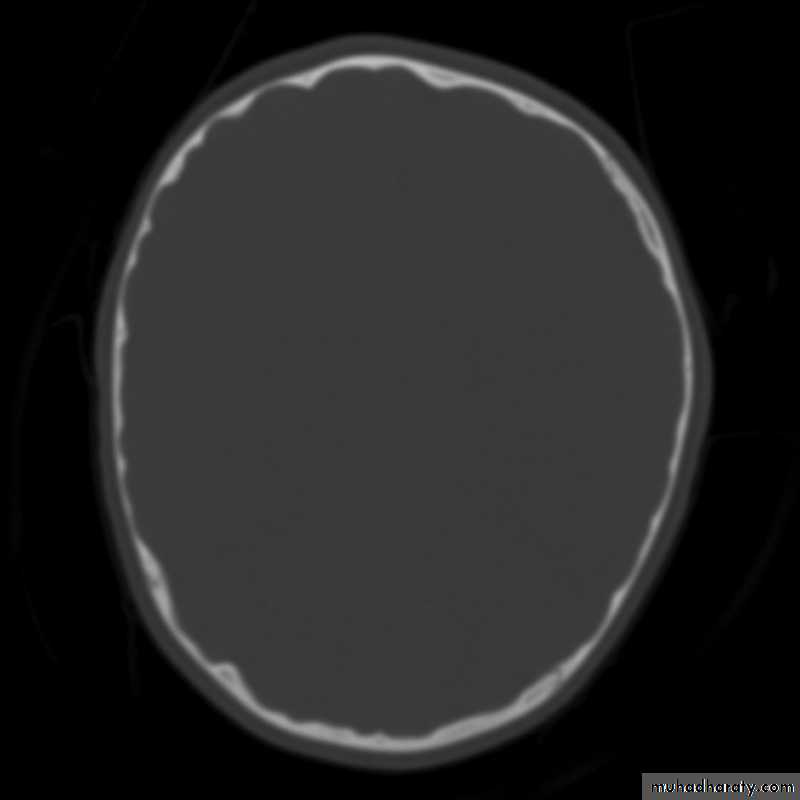

Skull X-ray findings in increased intracranial pressure

• Sutural separation in children.• ‘Copper-beating’ marking of the cranial vault.

• Thinning of dorsum sellae.

• Erosion of the posterior clinoid process.

Copper-beating’ marking